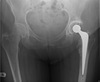

Hip replacement

AP Pelvis demonstrating a Left THR

Q